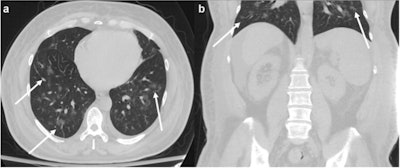

"As we have observed clinically within our major multihospital health system in New York City, many COVID-19 patients present with abdominal symptoms either in isolation or in combination with respiratory complaints," the group wrote. "These patients commonly undergo CT, with incidental findings of peripheral ground-glass opacities and/or consolidative opacities noted at the lung bases, which have been described in the setting of COVID-19."

Of the 62 patients, 19% were discharged and 81% were hospitalized. The most common abdominal symptoms were pain and nausea/vomiting, while common lung base CT findings were ground-glass opacities (95.2%) in a multifocal distribution (also 95.2%), according to the group.

"As our study suggests, the lower lobe predominance of these findings requires abdominal radiologists to keep COVID-19 diagnosis in mind even when patients present solely with abdominal complaints, and to suggest it as a differential diagnosis when appropriate," they concluded.